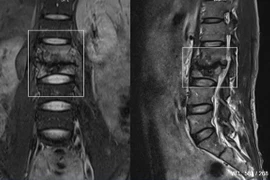

Sau khi vác bao xi măng 50 kg, người đàn ông xuất hiện đau lưng dữ dội, tê bì hai chân, mất cảm giác ngón chân, được bác sĩ xác định thoát vị đĩa đệm cấp, nguy cơ liệt, rối loạn đại tiểu tiện nếu không điều trị kịp thời.